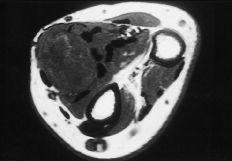

En los hemangiomas cavernosos fue frecuente el hallazgo de calcificaciones intravasculares, en ocasiones visibles radiográficamente. La RM fue específica, existiendo un patrón homogéneo de alta intensidad en relación con su contenido hemático estático (Fig. 3).

Los tumores vasculares aparecen con mayor frecuencia en la cabeza y cuello, aunque un 20% puede aparecer en las extremidades, y de ellos el 50% lo hace en las superiores.6,15,19,20 Según Myhre-Jensen23 los tumores de estirpe vascular es la tercera tumoración en frecuencia de una serie de 1.331 casos, de entre los cuales la localización en la mano o la muñeca supuso el 20%. Representan el 10% de los tumores de partes blandas de la mano.2,5,6,14,20,25,26,34,38 Hemos diagnosticado 55 casos, lo que significa un porcentaje algo más elevado que las series consultadas. El tipo histológico más frecuente ha sido el hemangioma cavernoso(20 casos). Se distingue por la formación de grandes canales vasculares mezclados con capilares de tamaño normal. En ellos es frecuente la formación de flebolitos en relación con el remanso vascular, pudiéndose observar en la radiología convencional.2,6,17,20,22,24-27,38 Los estudios de RM se caracterizan por un patrón homogéneo e hiperintenso en las secuencias T2 (Fig. 3). A veces dan imágenes serpenteantes en relación con los canales vasculares y los espacios entre ellos.17,29

Figura 3. Hemangioma que engloba los tendones flexores del dedo anular. Corte transversal en la palma de la mano, donde se constata un patrón homogéneo de alta intensidad de señal de resonancia (T1 potenciada).